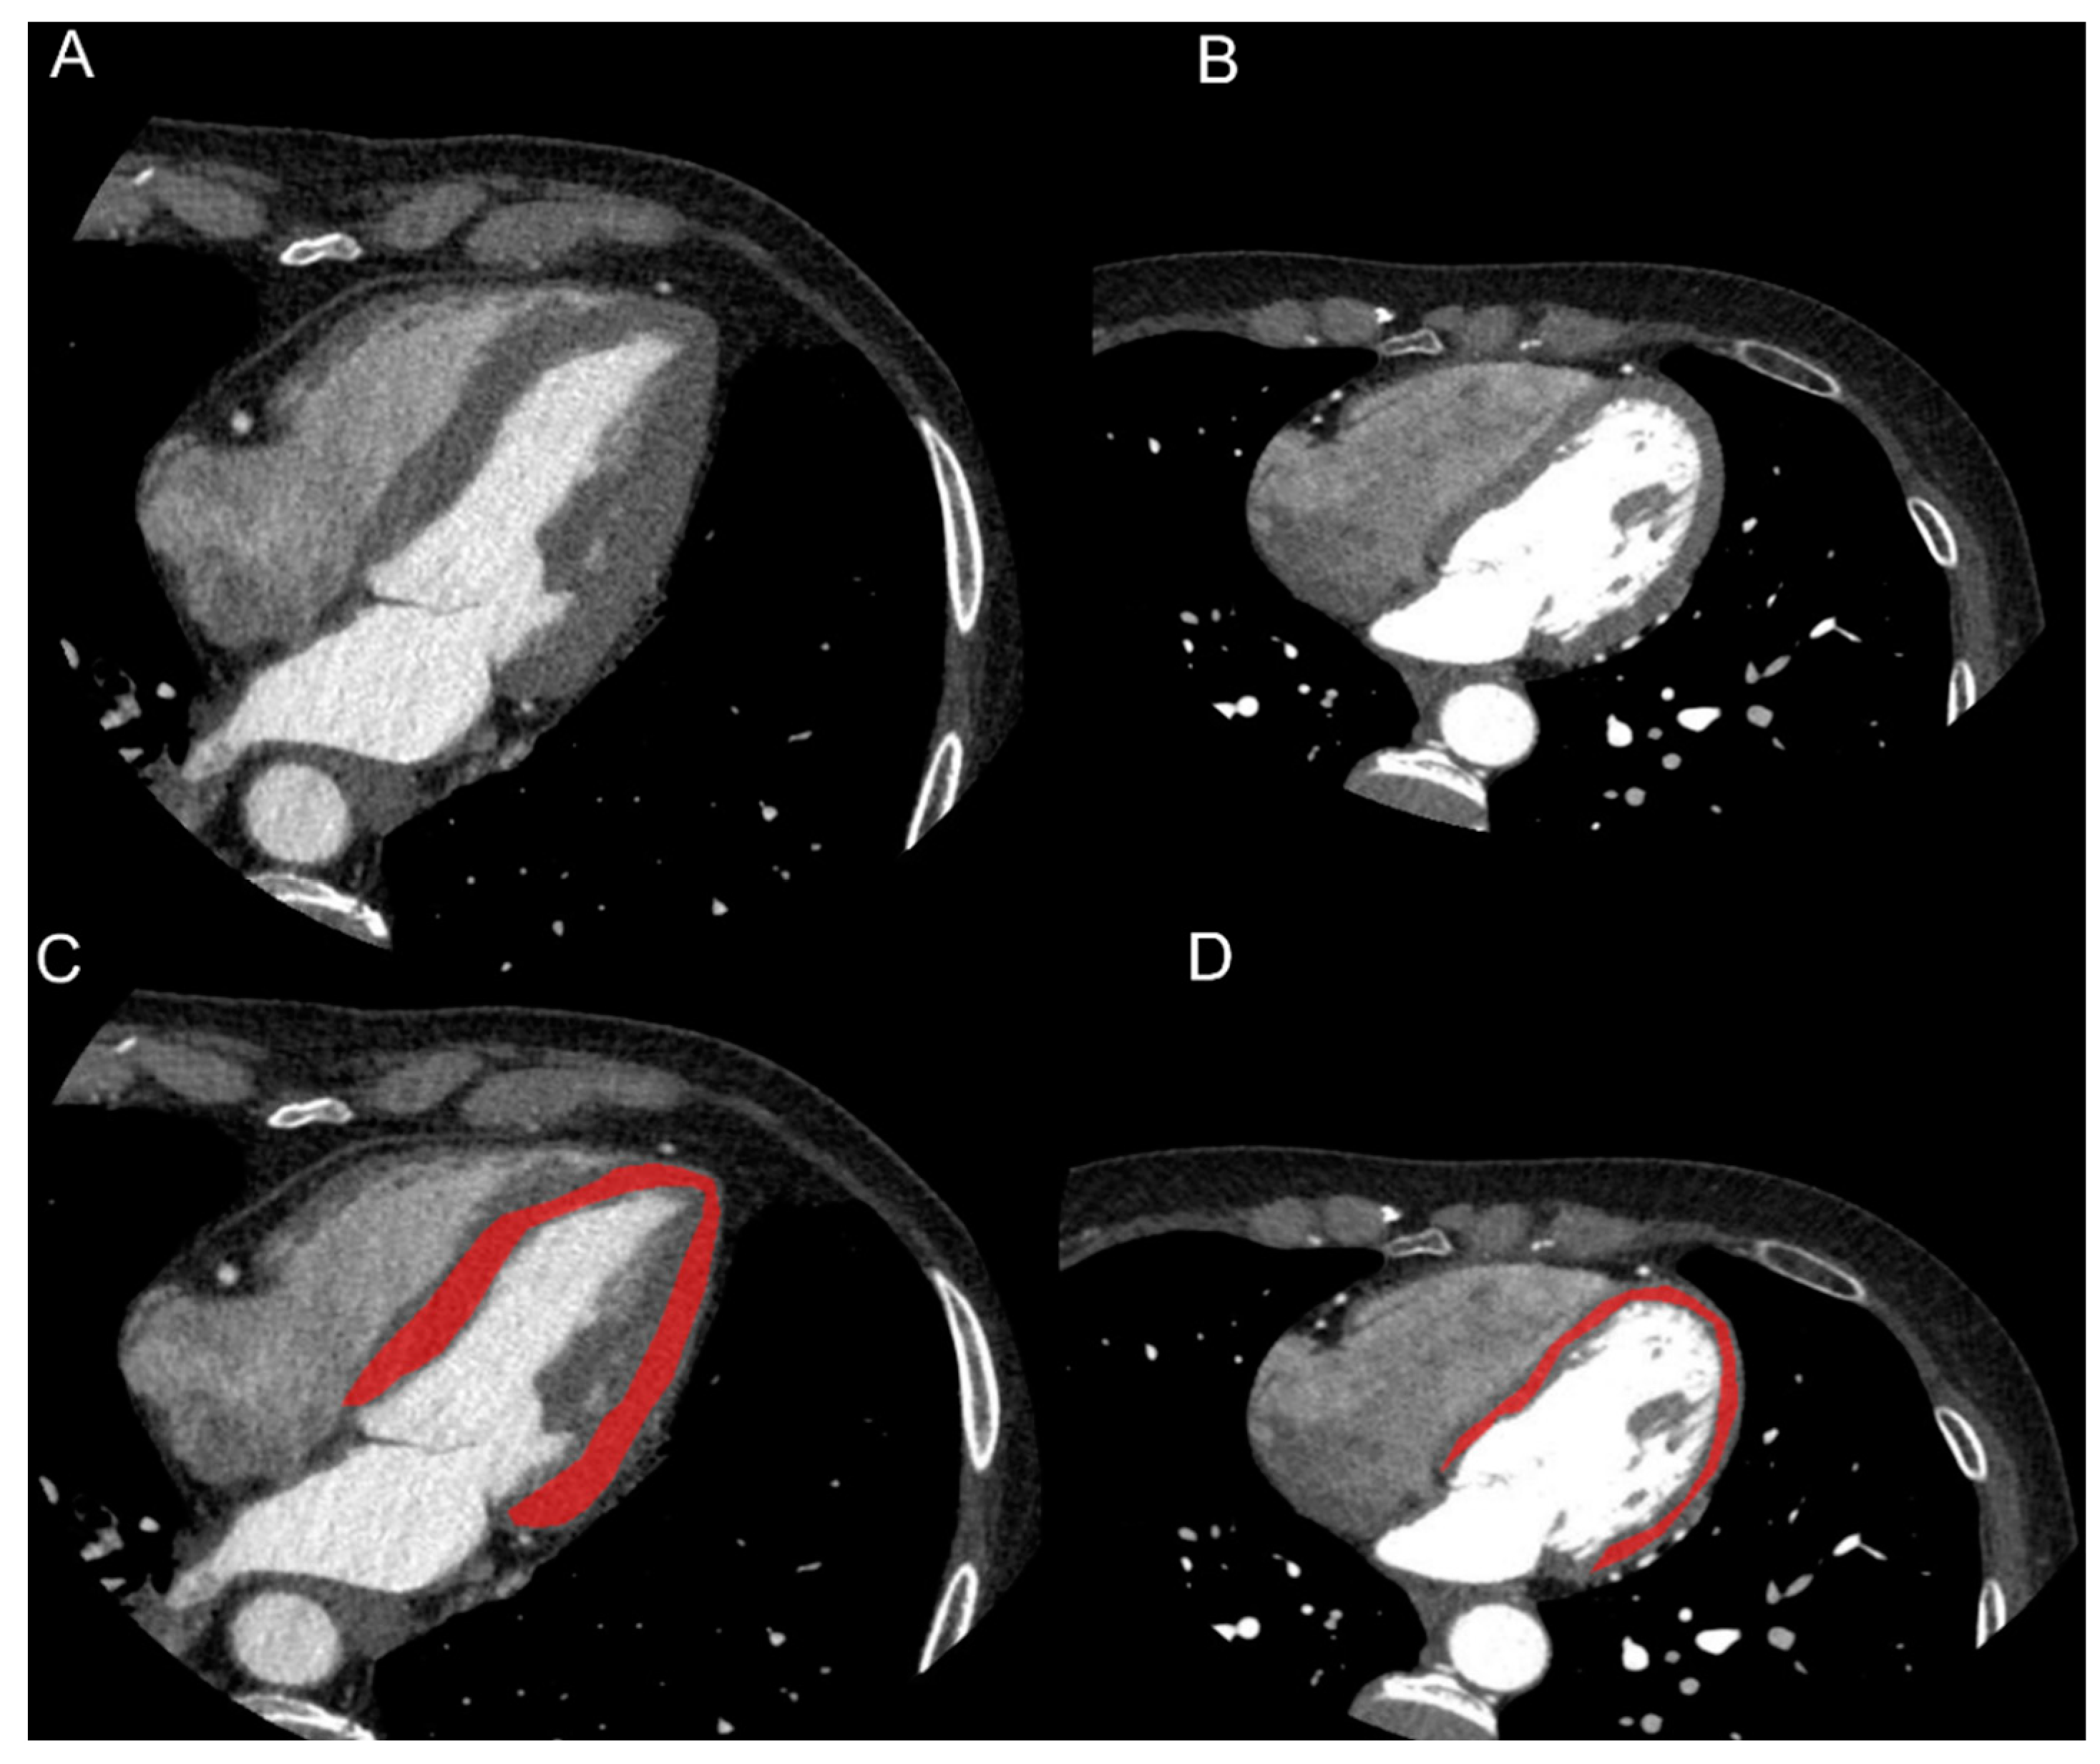

In one image per patient, on a 4-chamber view and at 75% of R-R interval, LV was segmented using a polygonal region of interest (ROI) by two radiologists in consensus. Care was taken to not include blood in LV cavity, epicardial fat, myocardial trabeculations or major coronary arteries in the ROI (Figure 1).

Figure 1.

Images and segmentation examples of cardiac CTs of patient with history of hypertension (HTN, (A–C)) and without history of hypertension (NC, (B–D)). On a 4-chamber view, LV was segmented using a polygonal region of interest (ROI). Care was taken in not including blood in LV cavity, epicardial fat or major coronary arteries. Clinical data of HTN patient were: male, 73 years old, BMI = 24.7 kg/m2, history of diabetes, dyslipidemia and hypertension, septum width: 14 mm. Clinical data of NC patient were: female, 61 years old, BMI = 18.9 kg/m2, smoker, familiarity with cardiovascular disease, no history of diabetes, dyslipidemia and hypertension, septum width: 8 mm.